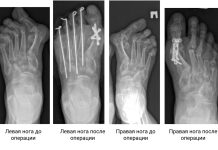

Новосибирские хирурги пересобрали женщине деформированные стопы

Более 20 лет ноги новосибирского врача-кардиолога постепенно принимали неестественную форму из-за ревматоидного артрита. Она даже переучилась на ревматолога, чтобы разобраться в мучившей её болезни,...